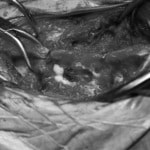

脊髄の減圧、脊柱管の再構築・安定化を目的に、片側椎弓切除術およびMatrixMANDIBLE Plateによる椎体固定を実施しました。

隣接椎体を架橋するようにプレートを設置しました。

術後レントゲン写真